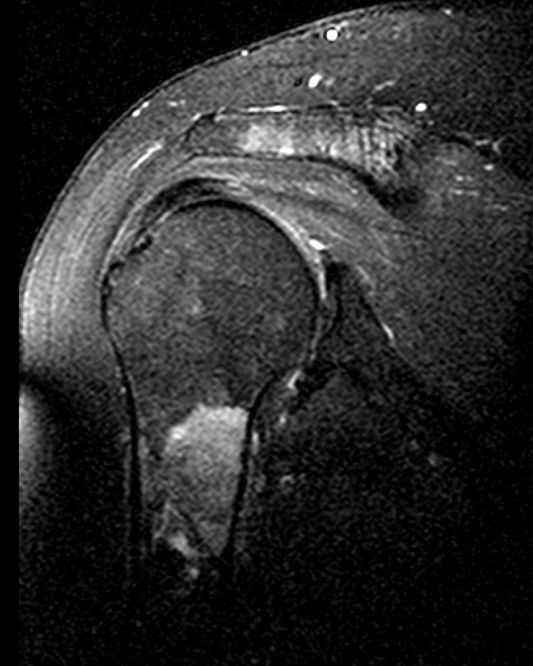

75-jähriger Mann, der wegen unklarer Schmerzen im

Nackenbereich abgeklärt wurde. Als Ursache der Knochenmetastasen wurde ein lokal

fortgeschrittenes Prostatakarzinom (PSA 143, Gleason 7) gefunden.![]() |

Das T2-Bild im MRT der HWS zeigt eine

Signalverstärkung im 7.HWK. Der Densbereich ist stark umgebaut.![]() | |||||||||||||||||||